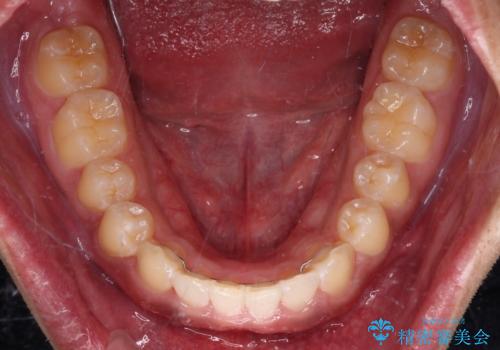

気になっていたデコボコや隙間は改善し、きれいな歯列に整えることができました。

咬合力が非常に強い方であったため、これ以上のディープバイトの改善は困難となりました。